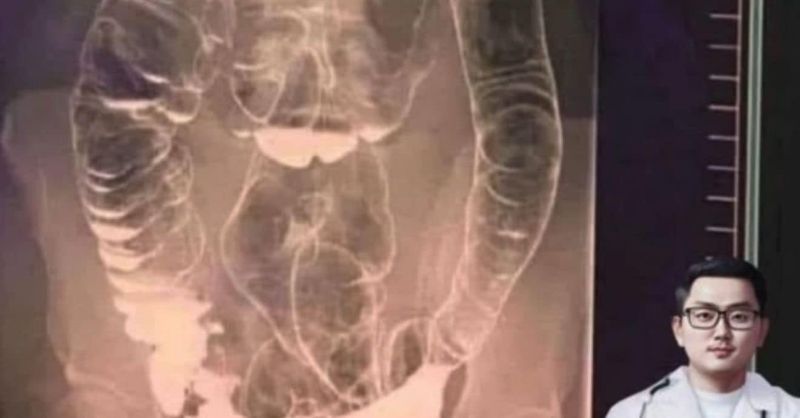

Why You Should Never Ignore Chronic Constipation: A Silent Killer To Your Digestive Health

Constipation might seem like just a minor inconvenience, but if left untreated, it can lead to serious health problems. Below is a real-life example that highlights the dangers...